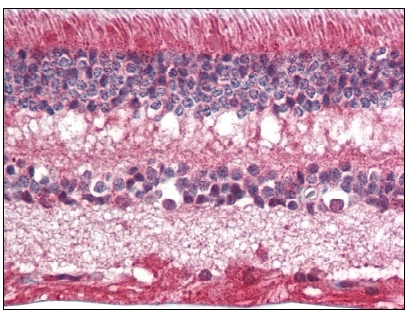

- Main image

- Experimental details

- Formalin-Fixed Paraffin-Embedded Human Eye, retina tissue using AP08544PU-N at 5 µg/ml.